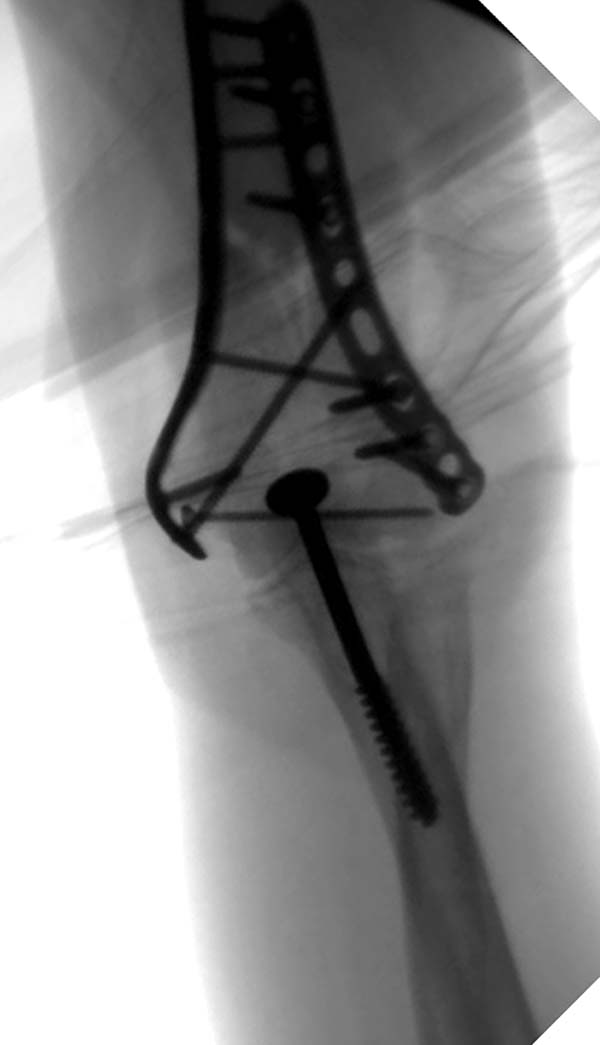

Примеры: первому более 15 лет фиксирован шурупом и tension band

technique, а второй перелом открытый больной 80 лет, после наружного

фиксатора в первом этапе и окончательная фиксация вторично. Третьий раз

внесуставная остеотомия...